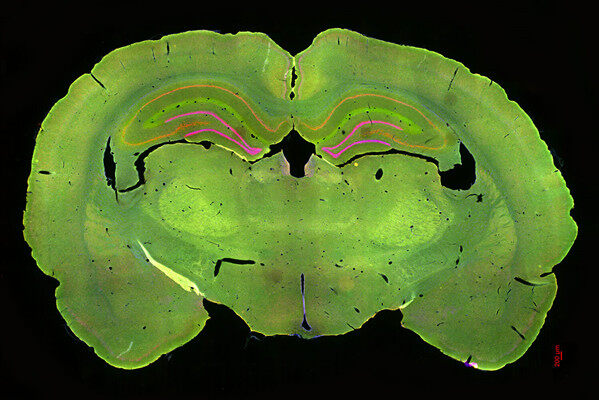

3D 组织成像

Mica 可使您在实验需要时从快速总览无缝切换到高分辨率观察。了解 Mica 如何帮助您识别去酪氨酸化微管蛋白阳性细胞,以及如何从微管蛋白网络的总览进入图像分割。